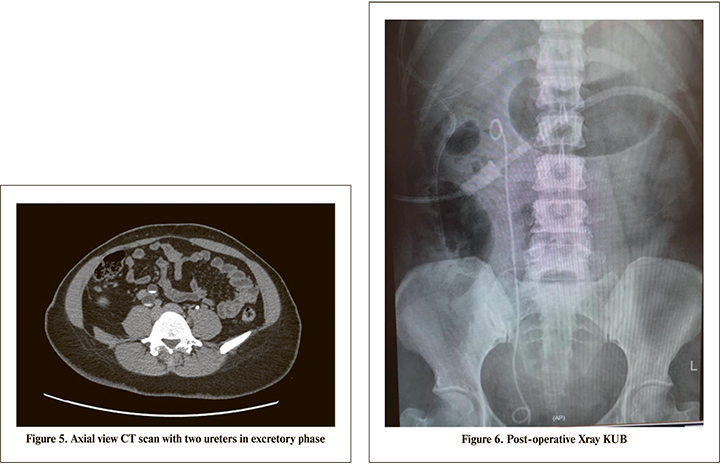

The patient is a 40 years old Malay lady presented with long history of right loin pain associated with radiating loin to groin pain with dysuria. Clinical examination showed no abdominal mass and bilateral kidneys were not ballotable with normal blood investigation results. An Xray KUB was done and showed right renal stone and multiple right distal ureteric stone (Figure 1). An ultrasound KUB performed and showed right hemorrhagic cyst with hydronephrosis. She had a non-contrast CT Kidney, ureter and bladder (KUB) performed and showed a lower moiety stone 1.6 cm x 2.3 cm with multiple distal ureteric stone with hydronephrosis and hydroureter (Figures 2,3 and 4). A CT Renal 4 phase was done and showed a right duplex with bifid ureters and obstructive uropathy due to distal ureteric stone and a right lower moiety renal calculus (Figure 5). She had a Diethylenetriamine pentaacetate (DTPA) scan and showed left kidney with 63.7% and right kidney 36.3% with upper moiety 85.4% and lower moiety 14.6% function. Subsequently a retrograde pyelogram and stenting was attempted but failed due to impacted distal ureteric stones. Hence, she was planned for primary Ureterorenoscopy (URS) and laser lithotripsy and laparascopic transperitoneal right heminephrectomy. Intraoperatively went smoothly and postoperative recovery was uneventful. Complete clearance of stones achieved (Figure 6). Her histopathology report confirmed features of non-functioning kidney with associated chronic inflammation. She was reviewed in the clinic 2 weeks postoperative for removal of stent and a subsequent clinic review with no signs of early and late complications.

Gold standard image modality for calculi is a non-contrast CT KUB. It has overtaken the role of CT Intravenous Uretherogram (IVU) in recent years. For this patient we had proceeded with CT kidney and excretory phase and proved of right kidney partial duplication system. Imaging is an important aspect and it gives a good visualization anatomy of right kidney and ureters to avoid misdiagnosis as abdominal cyst [5]. Therefore, it is important that duplex kidneys with hydronephrosis is considered in all patients with suspected abdominal cyst. Hence, patient had a URS and laser lithotripsy of calculi. It is reported to be an effective treatment modality for patients with symptomatic urolithiasis affecting a duplex collecting system. By understanding the anatomy, it prevented misleading to have normal URS during surgery as has been reported [6].